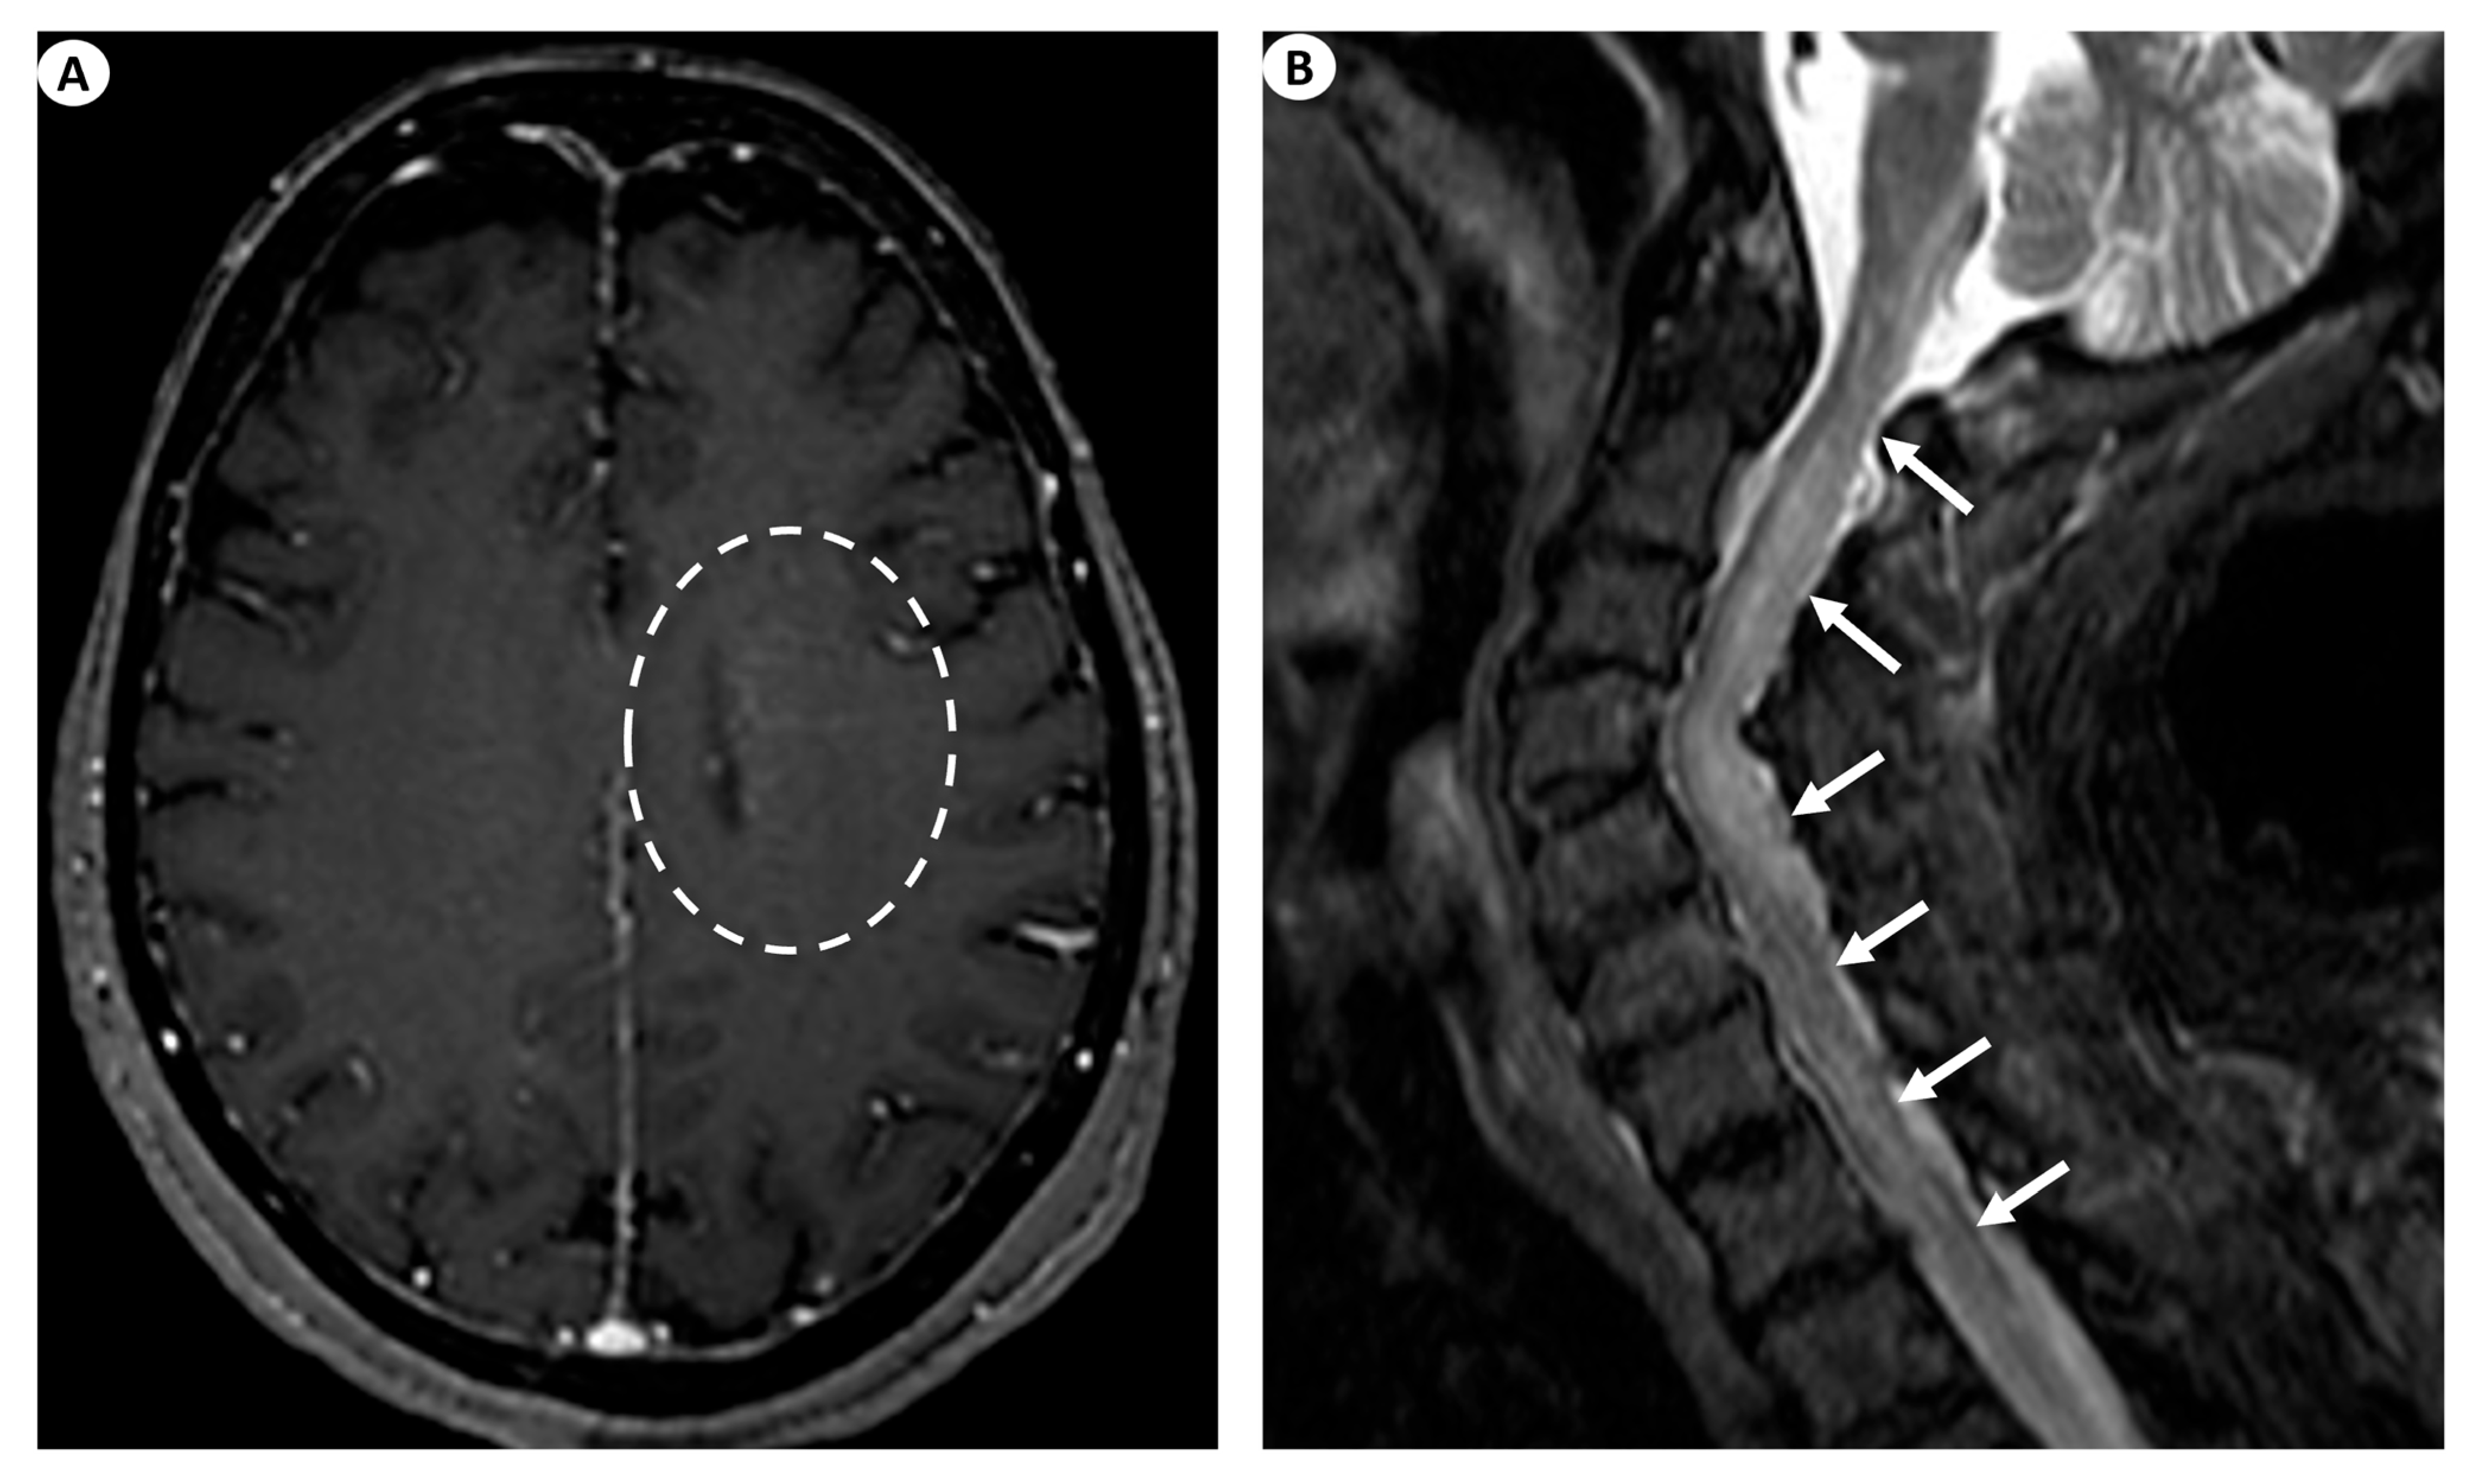

The most commonly encountered imaging manifestations include T2 signal abnormalities in the periventricular white matter. This finding’s presence has been documented in as low as 11.8% [9] and up to 75% [1] of patients. Nonetheless, besides the periventricular white matter, T2 signal abnormalities may also be recognized, affecting various different regions such as the basal ganglia, the thalami, the cortex, the brainstem, the cerebellum, and even the hippocampus. Specifically, in a 2021 study by Xiao et al. [9], basal ganglia and thalamic lesions were displayed in up to 41.2% of the patients, cortical lesions were displayed in 29.4% of the patients, while lesions were also depicted in the brainstem (23.5%), the cerebellum (5.9%), and the hippocampus (5.9%). Similarly, in a recent relevant study by Ke et al. (2024) [26], the evaluation of brain MRI examinations in 33 patients with GFAP astrocytopathy demonstrated T2/FLAIR abnormal hyperintensities in the vast majority of the cases studied (90.9%), most usually with a juxtacortical (54.5%) or a periventricular (48.5%) white matter localization, followed by lesions in the basal ganglia (45.5%), the brainstem (33.3%), the thalami (27.3%), and the cerebellum (6.1%). However, T2 periventricular white matter hyperintensities are a largely unspecific imaging finding.

On this note, a remarkable imaging finding considered a hallmark of GFAP astrocytopathy, which can be detected after intravenous gadolinium contrast agent injection, is a linear perivascular pattern of enhancement, which is usually located in the periventricular white matter in GFAP-enriched regions and extends outwards in a radial pattern [27,28]. This significant finding has been documented in as low as 23.5% [9] to up to 53% [2] of patients. Other manifestations of cerebral enhancement patterns may include leptomeningeal enhancement, encountered in as low as 33% [1] to up to 45.5% of patients [18], periependymal enhancement [28], as well as punctate or serpentine enhancement [4].

Likewise, GFAP astrocytopathy may also affect the spinal cord, producing signal abnormalities and abnormal enhancement [28]. Specifically, patients with clinical suspicion of myelitis may demonstrate extensive long-segment myelitis, illustrated as T2 signal hyperintensity with a caudocranial extension of more than three vertebral bodies with or without concomitant contrast enhancement with a linear, punctate, or patchy pattern [27]. To further analyze, in a study by Fang et al., a longitudinally extensive increase in the T2 signal was detected in up to 71% of patients with myelopathy, although up to 29% had a normal spine MRI study [1]. In the study by Xiao et al. on 15 patients undergoing spine MRI, 53.3% displayed the typical finding of longitudinal myelitic lesions, 26.7% had short myelitic lesions, and up to 20% had a normal spine MRI study. Central canal or leptomeningeal contrast enhancement was seen in 66.7% and 13.3% of patients, respectively [9]. In the study by Ke et al. (2024), an abnormal T2 hyperintense signal in the spinal cord was displayed in 19/27 cases undergoing spine MRI (70.4%), more commonly affecting long segments (55.6%) and the thoracic spinal cord (25.9%). Moreover, in the cases undergoing intravenous gadolinium injection, abnormal spinal cord enhancement was seen in 59.1%, most frequently exhibiting a leptomeningeal pattern of enhancement (54.5%), followed by enhancement in the central spinal canal (36.4%) [26].

Figure 3.

(A) Axial T1-weighted contrast-enhanced images following intravenous gadolinium injection demonstrate subtle periventricular linear contrast enhancement on the left cerebral hemisphere extending outwards in a radial pattern in a patient with GFAP astrocytopathy (dashed oval). (B) Sagittal fat-saturated T2-weighted images display abnormal signal hyperintensity extending craniocaudally from the cervicomedullary junction throughout the whole cervical spinal cord to the thoracic spinal cord (more than three vertebral levels affected), findings indicative of longitudinally extensive myelitis (arrows) in a female patient with GFAP astrocytopathy.